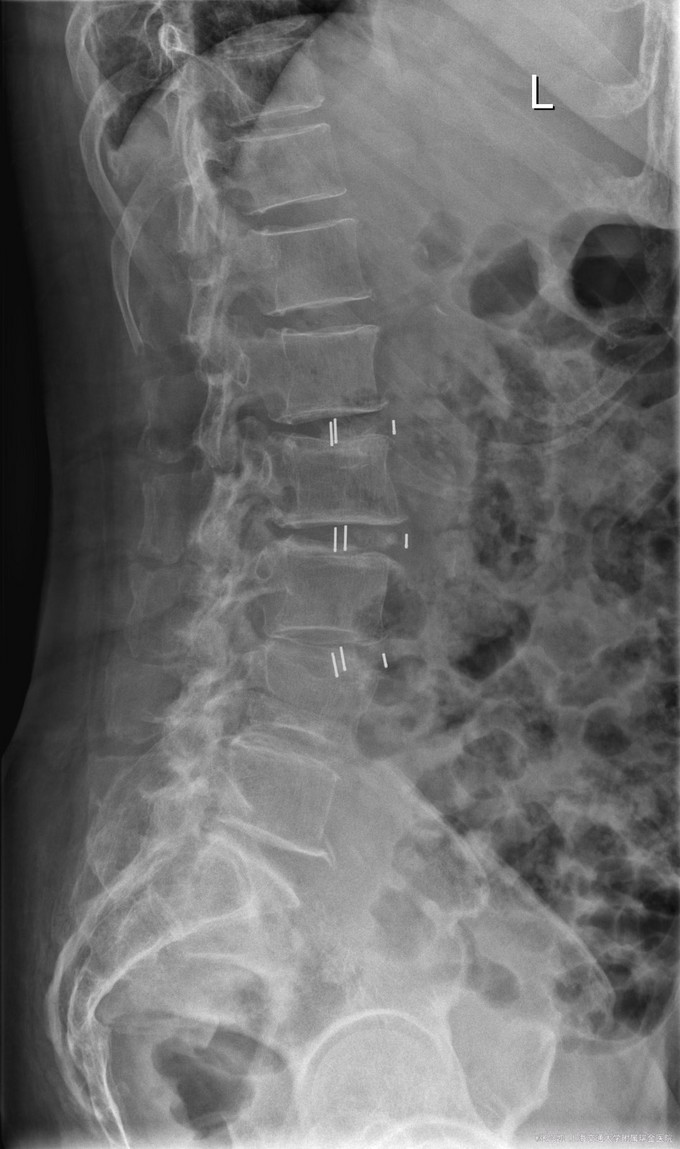

主诉:双下肢麻木7年,腰部酸痛无力 现病史:女性患者,70岁,患者诉腰背无力十几年,约于7年前无明显诱因下出现下肢麻木,站立位加重。后出现腰臀部僵硬,弓背加重,行走距离较短, 不足百米,几年前外院检查诊断为腰椎管狭窄,具体不详。

查体:侧弯畸形,右臀部及右下肢麻木疼痛,腰部活动受限,难以站立。右侧支腿抬高试验50°。双下肢肌力肌张力可。 辅助检查: 磁共振:L1-5,L5-S1腰椎椎间盘突出,腰椎退变,腰椎侧弯

诊断: 腰椎侧弯,腰椎间盘突出 治疗:1期微创侧路椎体融合术+2期 微创后路经皮内固定术

患者侧路微创术后神经压迫症状减轻,腰椎矢状位及冠状位腰椎力线得到改善,戴支具术后可早期下床活动,术后2周后行后路固定手术。